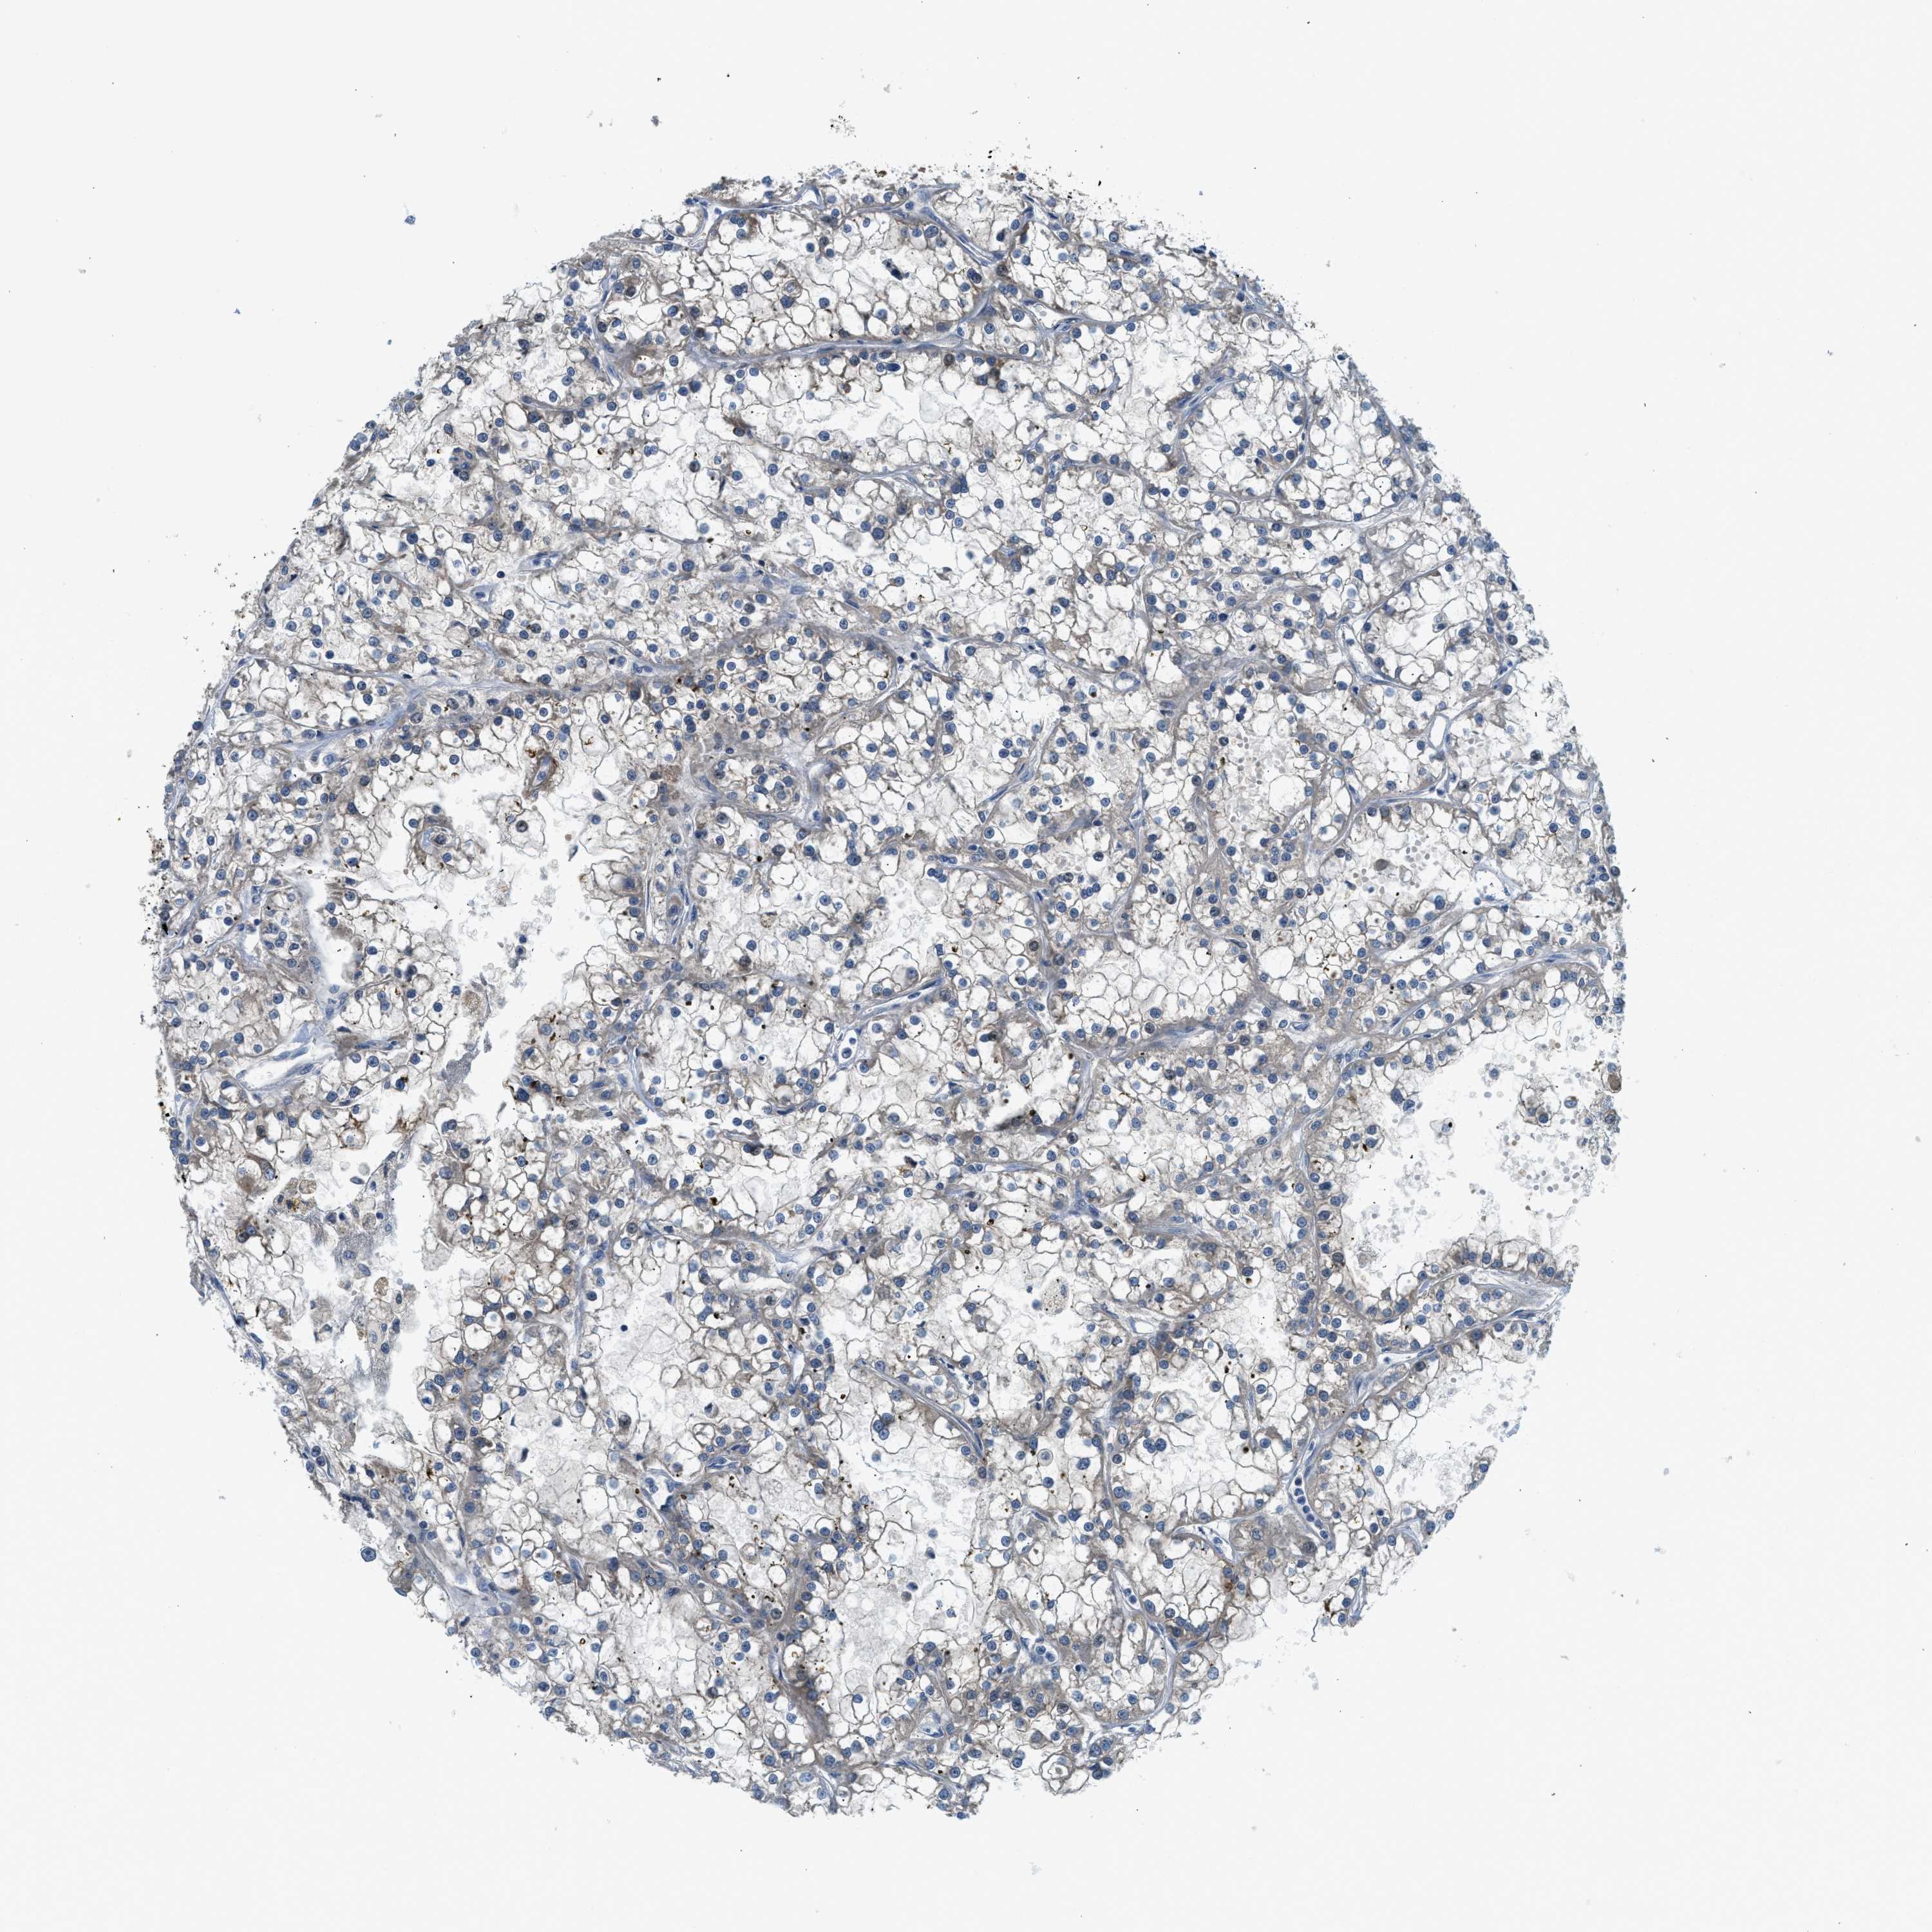

KIDNEY RENAL CLEAR CELL CARCINOMA (VALIDATION) - Interactive survival scatter ploti

The Survival Scatter plot shows the clinical status (i.e. dead or alive) for all individuals in the patient cohort, based on the same data that underlies the corresponding Kaplan-Meier plots. Patients that are alive at last time for follow-up are shown in blue and patients who have died during the study are shown in red.

The x-axis shows the expression levels (FPKM) of the investigated gene in the tumor tissue at the time of diagnosis. The y-axis shows the follow-up time after diagnosis (years). Both axes are complimented with kernel density curves demonstrating the data density over the axes. The top density plot shows the expression levels (FPKM) distribution among dead (red) and alive patients (blue). The right density plot shows the data density of the survived years of dead patients with high and low expression levels respectively, stratified using the cutoff indicated by the vertical dashed line through the Survival Scatter plot. This cutoff is automatically defined based on the FPKM cutoff that minimizes the p-score. The cutoff can be changed by dragging the vertical line or by entering a cutoff value in the square labeled "Current cut-off".

Under the Survival Scatter plot the p-score landscape (black curve; left axis) is shown together with dead median separation (red curve; right axis). Dead median separation is the difference in median mRNA expression between patients who have died with high and low expression, respectively. It is calculated as follows: median FPKM expression of dead patients with high expression - median FPKM expression of dead patients with low expression. This is intended to aid the user in visually exploring custom cutoffs and the associated p-scores and dead median separation.

Individual patient data is displayed and can be filtered by clicking on one or more of the category buttons on the top of the page. Categories describing expression level and patient information include: high, low, alive, dead, female, male and tumor stages. The scale of the x-axis can be toggled between linear and log-scale by clicking on the "x log" button. Mouse-over function shows TCGA ID, patient information and mRNA expression (FPKM) for each patient.

& Survival analysisi

Kaplan-Meier plots summarize results from analysis of correlation between mRNA expression level and patient survival. Patients were divided based on level of expression into one of the two groups "low" (under cut off) or "high" (over cut off). X-axis shows time for survival (years) and y-axis shows the probability of survival, where 1.0 corresponds to 100 percent.

KCNK1 is potential prognostic, high expression is unfavorable in Kidney Renal Clear Cell Carcinoma (validation)

Best expression cut offi

Based on the FPKM value of each gene, patients were classified into two groups and association between prognosis (survival) and gene expression (FPKM) was examined. The best expression cut-off refers the FPKM value that yields maximal difference with regard to survival between the two groups at the lowest log-rank P-value. Best expression cut-off was selected based on survival analysis .

When clicking on this number, the vertical dashed line indicating cut-off, the interactive survival plot, and the Kaplan-Meier curve will be adjusted to show results based on the best expression cut-off.

: 15.1

P scorei

Log-rank P value for Kaplan-Meier plot showing results from analysis of correlation between mRNA expression level and patient survival.

N/A

TCGA RNA samplesi

RNA-seq data is reported as average FPKM (number Fragments Per Kilobase of exon per Million reads), generated by the The Cancer Genome Atlas (TCGA) .

Normal distribution across the dataset is visualized with box plots, shown as median and 25th and 75th percentiles. Points are displayed as outliers if they are above or below 1.5 times the interquartile range. FPKM values of the individual samples are presented next to the box plot.

Average pTPM 15.9

Number of samples 100